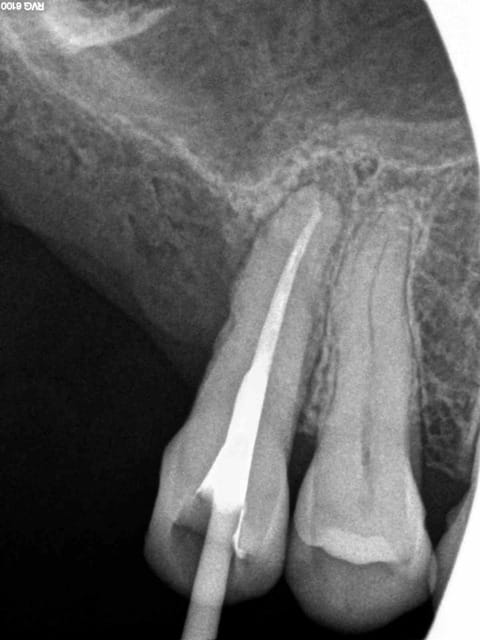

Je prends en general une cone en place scellée pour verifier que tout est ok au niveau radio.

Puis je thermocompacte et j'ai souvent des puffs apres .

Capture d  cran 2014 12 21   18.01 - Eugenol